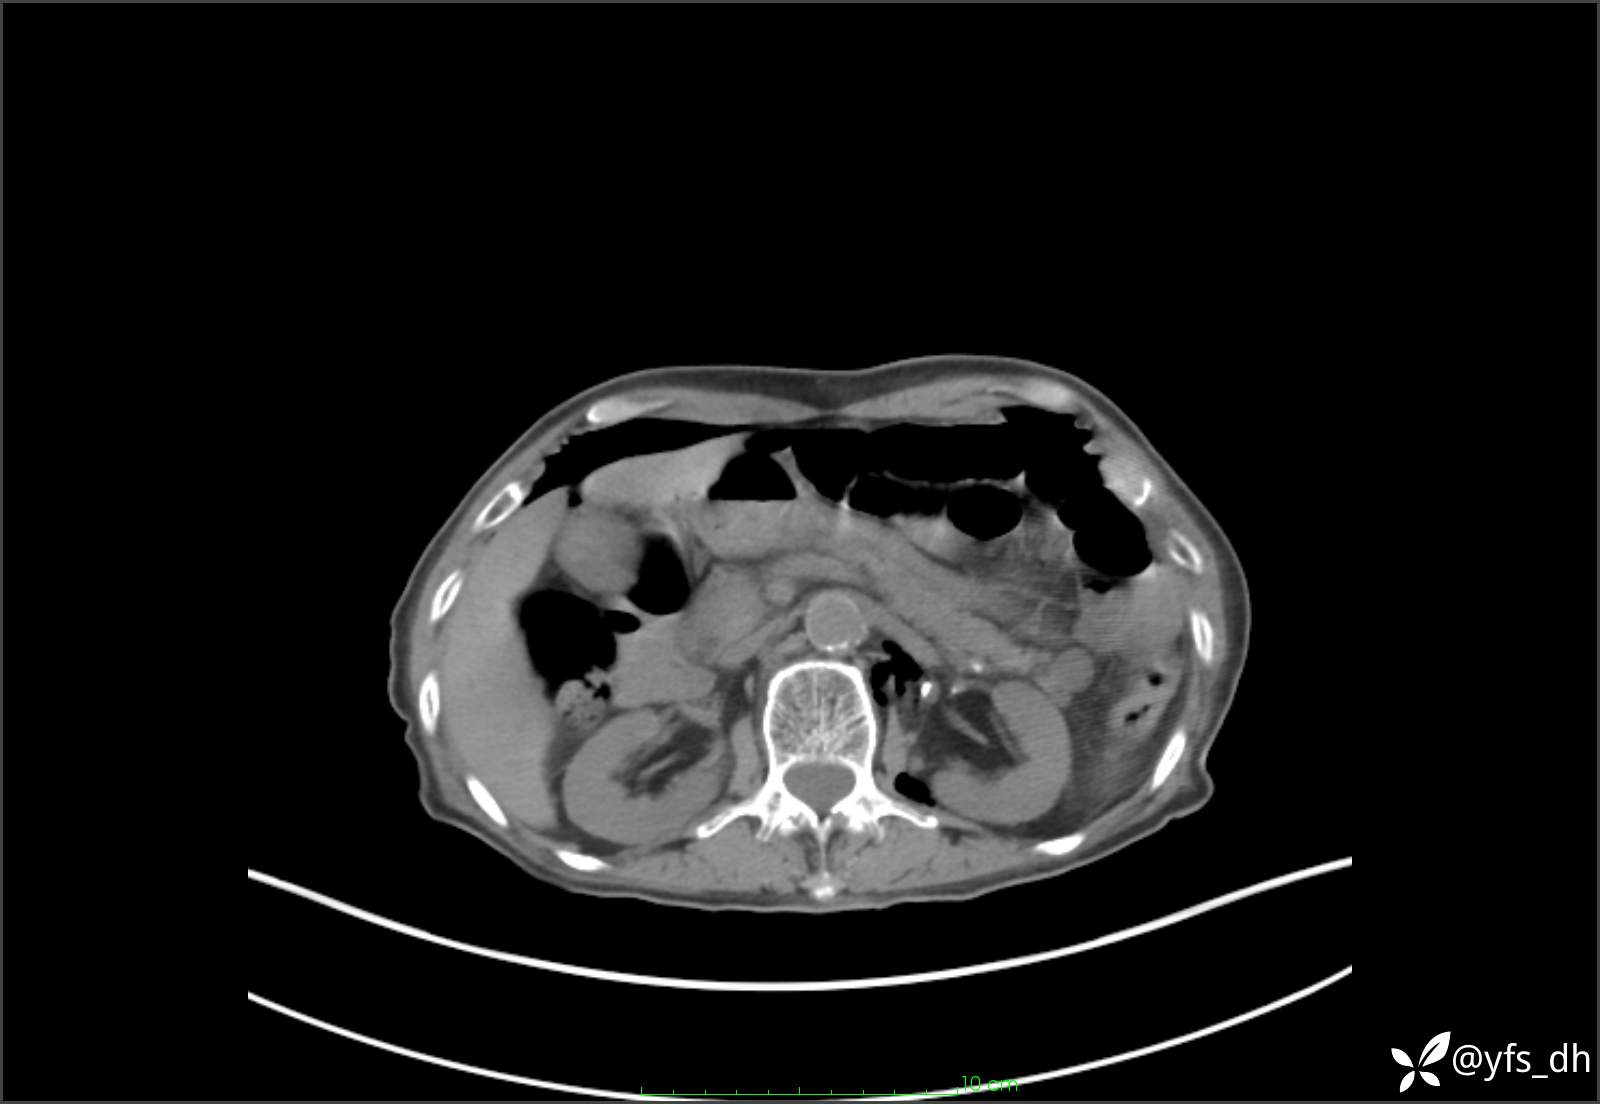

1.简要病史:患者4天前突发上腹部疼痛不适,但可以忍受。3小时前饭后突然加重,不能忍受后就诊。

2.简要手术记录:术中见腹盆腔大量肠液及粪便,乙状结肠中下段见一约3cm的破口。